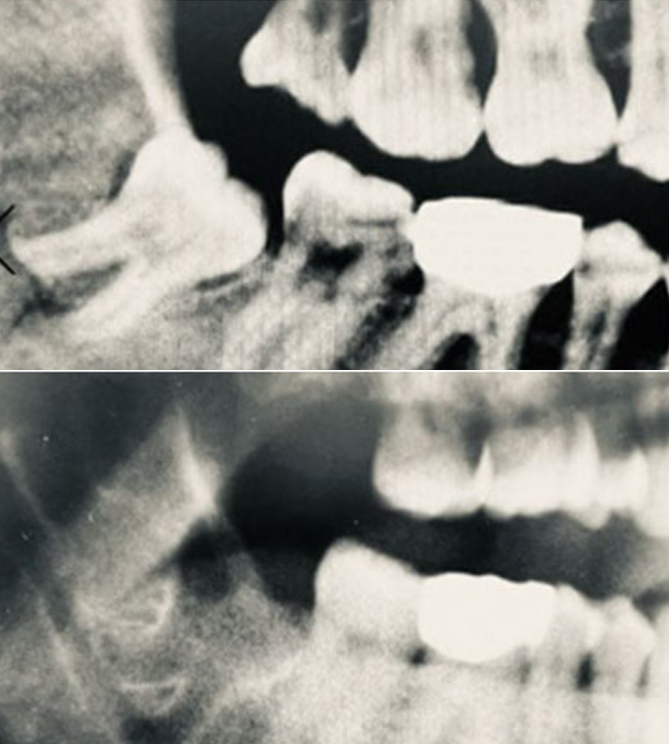

전후사진